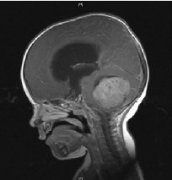

髓母细胞瘤 是位于小脑的脑肿瘤,小脑是控制平衡,协调和其他复杂运动功能的大脑部分。髓母细胞瘤较常生长在小脑的中央部位,而在小脑的外部部分则...

髓母细胞瘤 是儿童中较常见的恶性脑肿瘤。根据定义,髓母细胞瘤发生在小脑中,小脑是位于头骨基部的脑部的一部分,位于脑干上方。小脑参与许多功能...

髓母细胞瘤 是一种癌性脑肿瘤。它在小脑中发育,小脑是头骨底部附近的大脑的一部分。髓母细胞瘤可以扩散到中枢神经系统 (大脑和脊髓)。儿童大多...

髓母细胞瘤,这种起源与胚胎残余细胞的肿瘤可发生在脑组织的任何部位,但多数生长在四脑室顶之上的小脑蚓部,是中枢神经系统恶性程度较高的肿瘤之...

髓母细胞瘤是后颅窝比较常见的恶性肿瘤,也是中枢神经系统恶性程度较高的神经上皮性肿瘤之一。它的细胞形态很像胚胎时期的髓母细胞,因此得名。髓母...